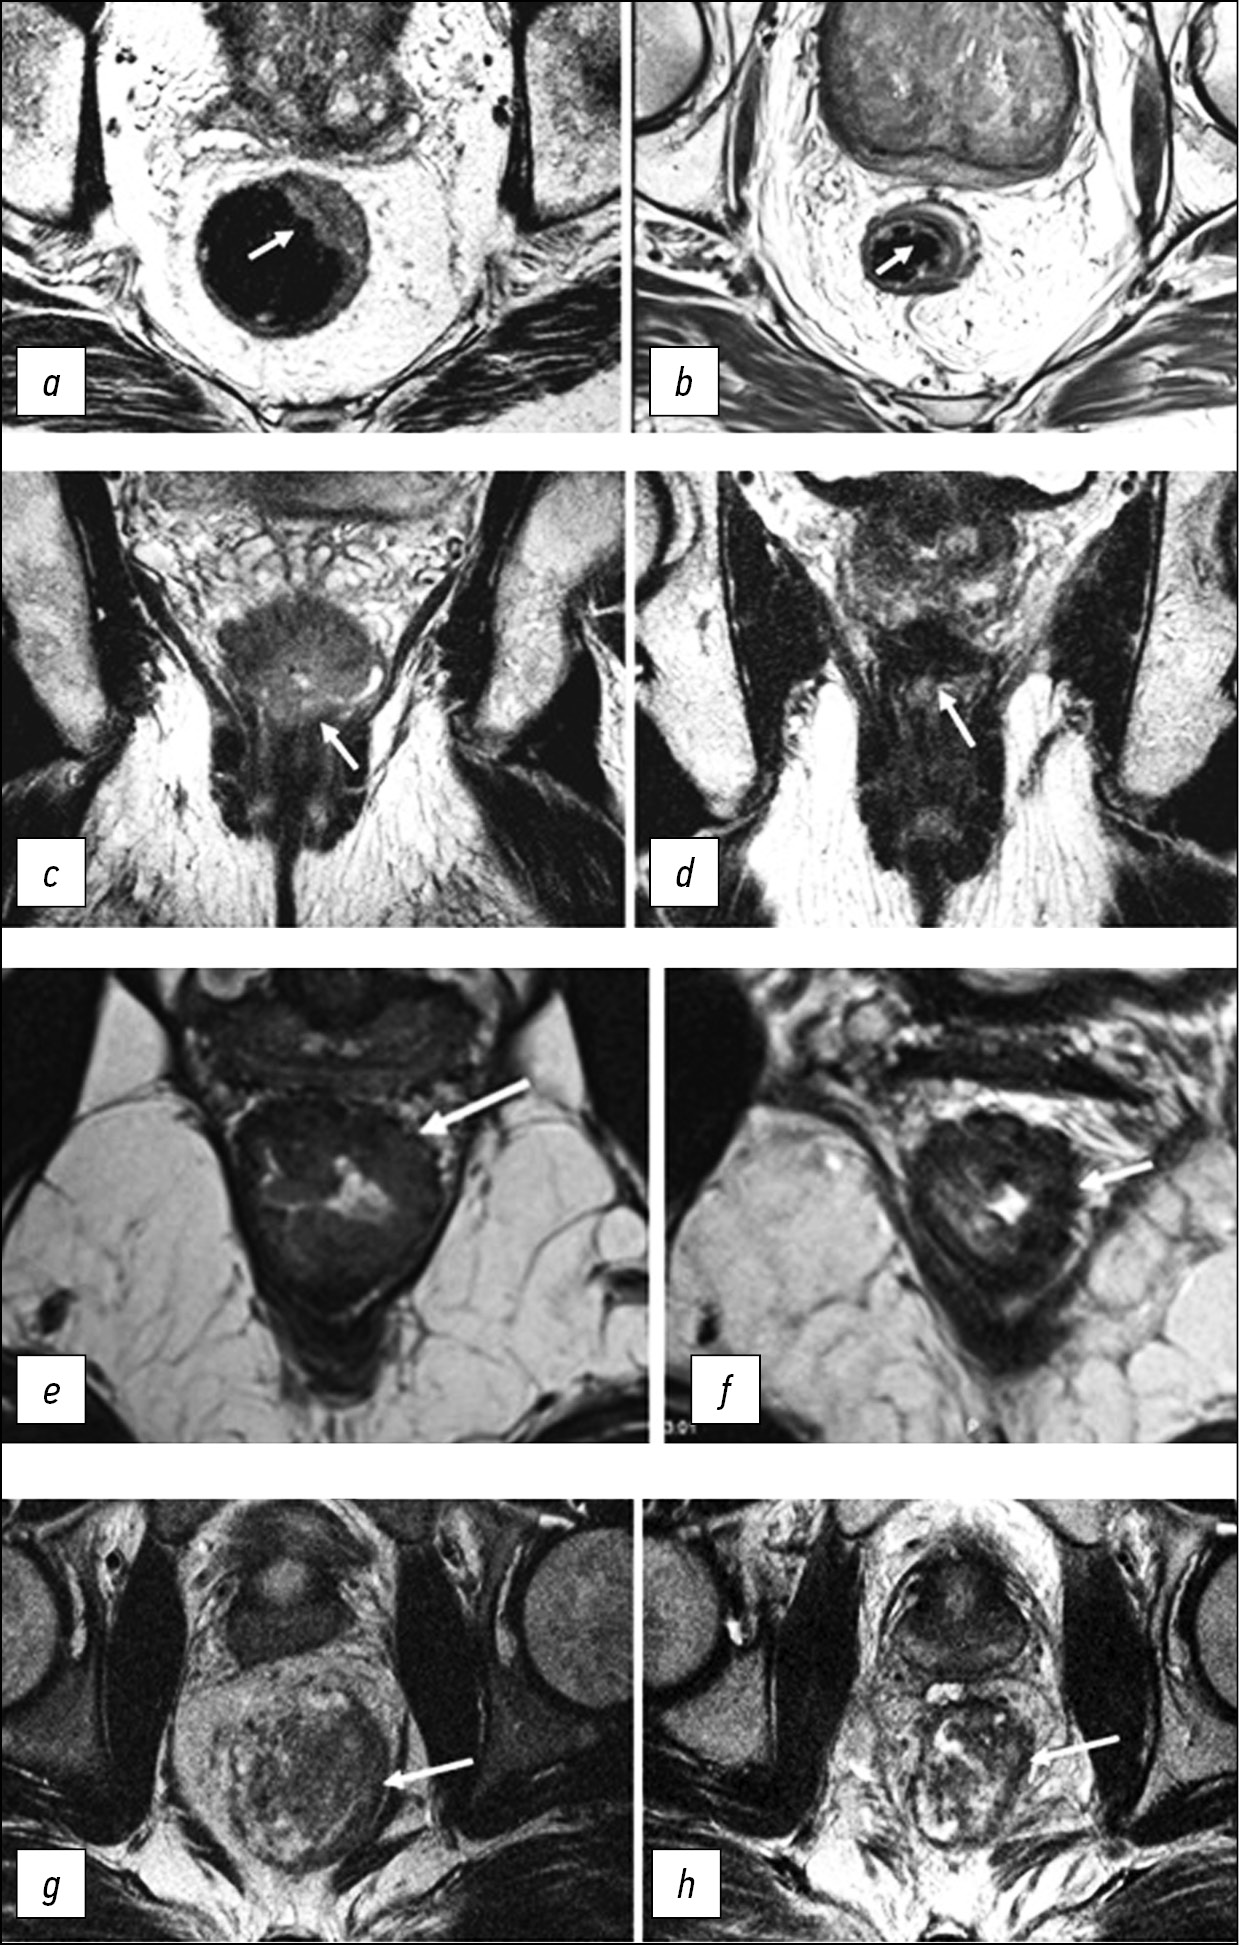

Tumor regression grading (TRG) is a system for assessing the response to neoadjuvant chemoradiotherapy, derived from a modification of the Mandard pathological staging (MRI TRG). It involves a qualitative assessment of the ratio of a low MR signal from fibrous tissue and a medium-intensity signal from a residual tumor on T2-WI.

- mrTRG1 (complete response) means no macroscopic signs of residual tumor tissue/a minimal area of fibrosis is visualized (thin scar).

- mrTRG2 (significant/almost complete response) means the presence of dense fibrous scar, with no signs of tumor tissue visualized (according to pathological data, tumor cells are absent/single in settings of dense fibrosis).

- mrTRG3 (moderate response) means fibrosis predominates (>50%), while an MR signal of medium intensity is visualized, which is characteristic for tumor tissue.

- mrTRG4 (minimal response) means the MR signal from the tumor tissue predominates, combined with a small/minimal structural fibrosis.

- mrTRG5 (no response/progression) means only an MR signal of medium intensity, characteristic of tumor tissue, without signs of fibrosis (Fig. 5).

Fig. 5. Assessment of tumor regression on high-resolution T2-WI using TRG. TRG١: (a) Tumor located at the 12–2 o’clock position before neoadjuvant chemoradiation therapy (arrow); (b) after treatment, the tumor is replaced by a linear area of submucosal fibrosis. TRG2: (c) Tumor in the lower ampullary rectum before chemoradiation therapy (arrow); (d) after treatment, the tumor is determined as an area of thick fibrosis (arrow), without macroscopic MR signs of tumor. TRG3: (e) Semicircular tumor in the lower ampullary rectum before chemoradiation therapy (arrow); (f) after treatment, the tumor has a mixed MR signal with a predominance of a low-intensity signal, characteristic of fibrosis, and preservation of macroscopic areas of a tumor MR signal of medium intensity (arrow). TRG4: (g) Tumor before chemoradiation therapy (arrow); (h) after treatment (arrow), there are no signs of response to treatment; the MR signal of the tumor tissue persists.

Current clinical experience shows that this system has poor correlation with pathological TRG, limited positive predictive value of pCR and poor reproducibility with low kappa values [29, 30]. Therefore, further research is required to find ways of improving its diagnostic efficiency.